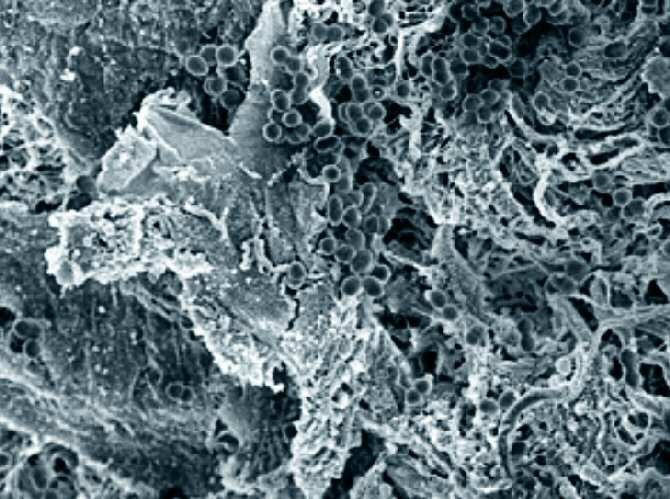

Los genes para la resistencia a antibióticos se transportan en fragmentos circulares de ADN llamados plásmidos. Una célula bacteriana que tiene un plásmido puede transmitirlo, junto con genes de resistencia a antibióticos y otros rasgos, a una célula que no lo tiene, a través de un proceso bacteriano conocido como conjugación.![[Img #3761]](upload/img/periodico/img_3761.jpg)